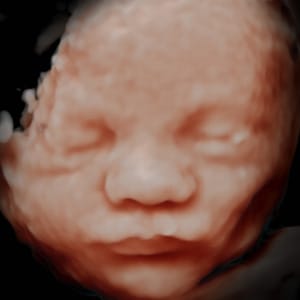

Con avances tecnológicos continuos, las ecografías 8K han llevado esta experiencia visual a un nivel completamente nuevo. Sin embargo, en el mundo de la innovación médica, siempre hay espacio para la mejora. Es aquí donde entra en juego Be·ia, una máquina revolucionaria que transforma las ecografías en imágenes hiperrealistas que capturan la esencia misma de la vida en desarrollo. En este artículo, exploraremos por qué las ecografías 8K, aunque impresionantes, se quedan cortas en comparación con la asombrosa precisión y detalle de las imágenes ofrecidas por Be·ia.

En un mundo donde la tecnología evoluciona constantemente, Be·ia emerge como una solución innovadora que supera las limitaciones de las ecografías tradicionales en 8K. Be·ia utiliza un enfoque revolucionario al procesamiento de imágenes para recrear imágenes hiperrealistas que capturan no solo la apariencia física, sino también la esencia emocional del bebé en desarrollo.

A diferencia de las ecografías 8K, que pueden parecer frías y clínicas, las imágenes hiperrealistas de Be·ia transmiten la emoción cruda y real del embarazo. Cada pequeño movimiento, cada gesto y cada sonrisa del bebé se capturan con una autenticidad que va más allá de lo que la resolución por sí sola podría lograr. Esto brinda a los padres una oportunidad única para sentirse aún más conectados con su futuro hijo.